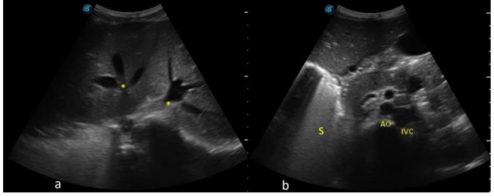

On radiological examination, Echocardiography revealed a common atrium due total absence of the interatrial septum, mild tricuspid regurgitation, preserved ejection fraction of 58.9% and preserved ventricular geometry (Figure 1). Ultrasonography of the abdomen revealed transposition of the major visceral organs (the spleen and stomach are located on the right side). Liver is enlarged occupying the whole upper part of the abdomen. There are two main hepatic veins (with 3 branches, each) joining before draining directly to the common atrium (CA) and left-sided inferior vena cava (IVC) (Figure 2).

Figure 1: Echocardiography showing common atrium *